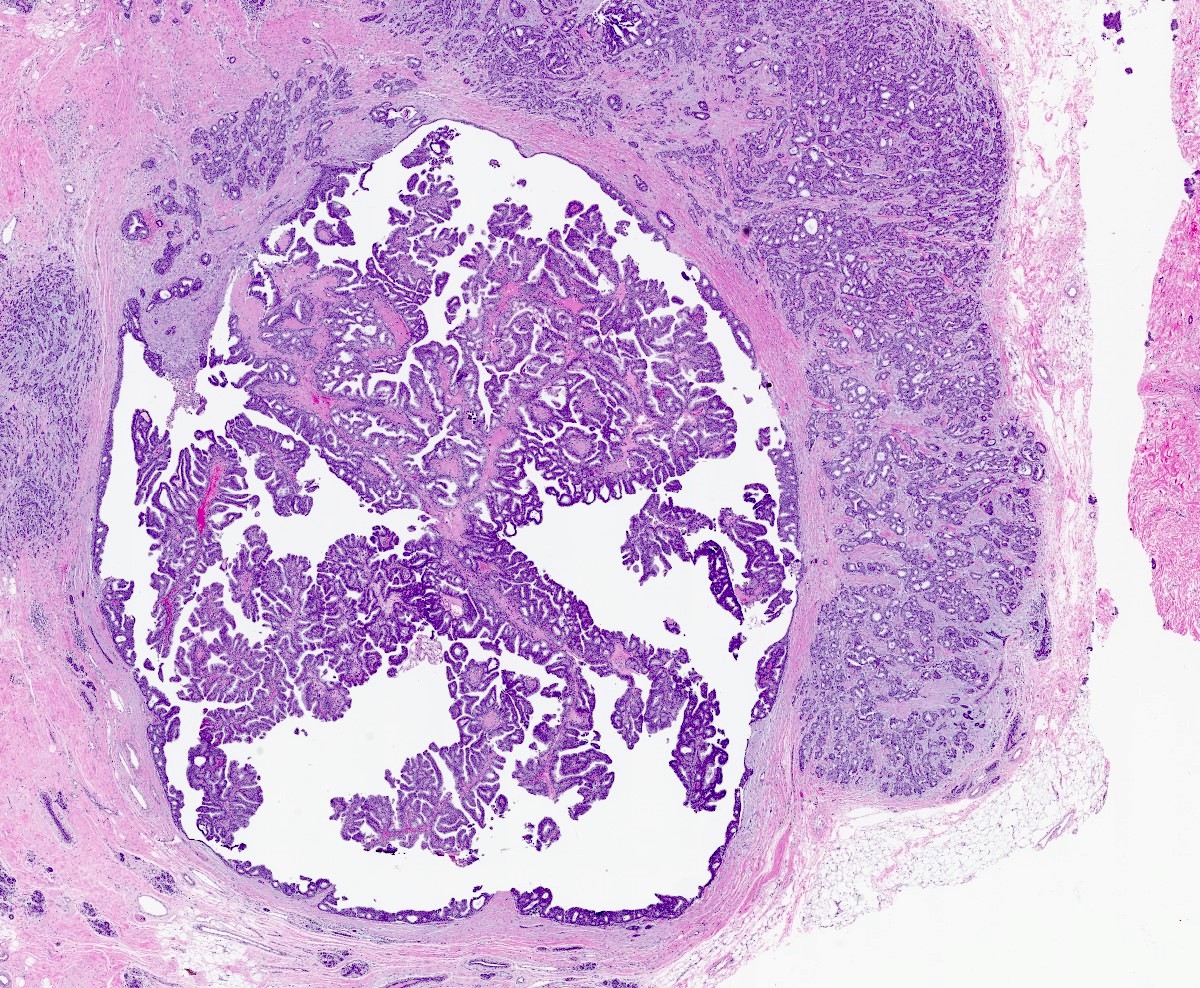

- Papillary tumor with pushing borders, may be within a cystically dilated duct, surrounded by a thick fibrous capsule (Histopathology 2008;52:20, Mod Pathol 2021;34:1044, Virchows Arch 2022;480:5)

- Delicate papillary fronds with fibrovascular cores lined by cuboidal to columnar epithelial cells with low to intermediate grade atypia

- Cribriform and solid architecture may be present

- Most show complete lack of myoepithelial cells along the papillae and around the periphery of the tumor (Am J Surg Pathol 2006;30:1002, Am J Surg Pathol 2011;35:1)

- Invasive carcinoma is defined as the presence of neoplastic cells infiltrating beyond fibrous capsule (Mod Pathol 2021;34:1044)

Microscopic (histologic) images

Contributed by Kristen E. Muller, D.O. , Mariel Molina Nunez, M.D. and Julie Jorns, M.D. (Case #518)